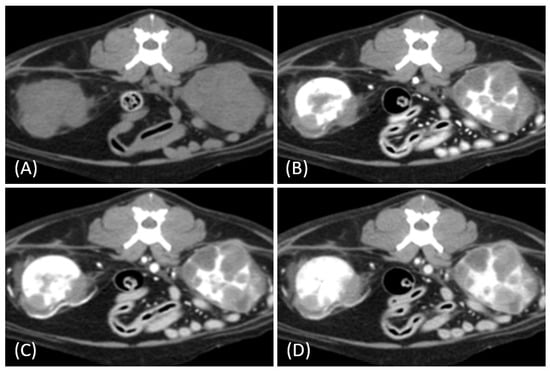

Figure 3.

(A) Pre-contrast, (B) corticomedullary phase, (C) nephrographic phase, and (D) delayed nephrographic/early excretory phase contrast-enhanced computed tomography (CT) images of a cat with bilateral renal and small intestinal lymphoma. The right kidney shows an infiltrative mass (black arrow), while the left kidney has an expansile mass (white arrow). Both tumors are homogeneous and hypodense, demonstrating progressive enhancement.